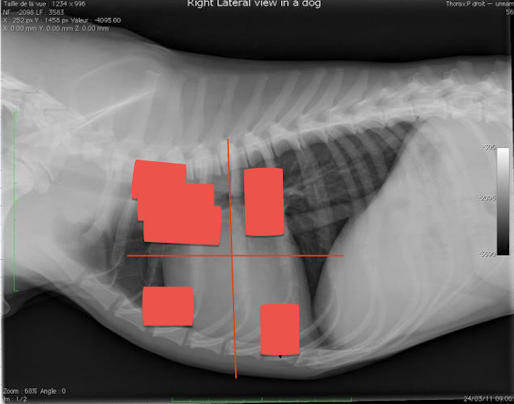

What are seen in each quadrant?

Label